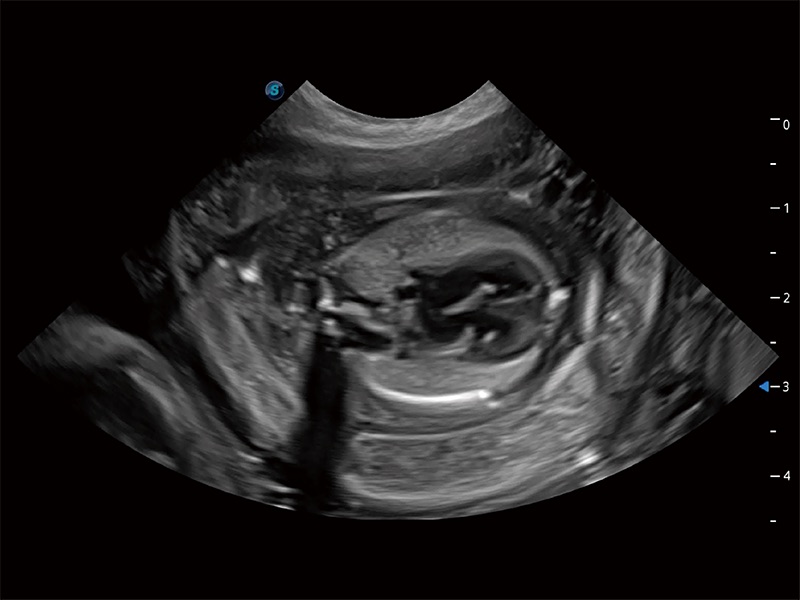

动物是人类最亲密的朋友和最值得信赖的伙伴。云顶集团官网也一直致力于探索动物专用的超声影像解决方案。全新推出的ProPet系列,是云顶集团官网在动物超声影像智能化、专业化、精准化的一次跨越式革新。动物不能用言语来表述自己的不适,通过超声影像,ProPet系列搭建了动物医生与不同物种沟通的“桥梁”,为动物医生注入了“治愈之力”。 ProPet 80 是云顶集团官网匠心打造的一款高端动物专用彩超,采用性能卓越的全新硬件架构,极大提升超声系统的运行效率和数据处理能力,帮助动物医生从容应对日益增多的挑战性病例和日益多样化的临床需求。

高性能和先进的临床应用工具可以为动物医生提供临床信心。ProPet 80 搭载了先进的腹部和浅表应用工具,帮助医生在日常临床实践中发挥前所未有的作用。

ProPet 80 全新的动物超声智能软件和丰富的探头群,为动物医生提供了高清晰度和精细分辨率的图像,无论在宠物、马科、畜牧还是实验室动物等应用中都可以轻松应对,为您的日常工作带来满意的体验。